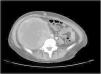

A 38-year-old woman with NF1 presented at the hospital’s emergency department with lower back pain of 3 months’ duration and constitutional symptoms. Physical examination of the abdomen revealed a large, hard mass on the right flank that was painful to the touch. She also had multiple café-au-lait spots, generalized freckles, mainly affecting the trunk and with a tendency to cluster in the area of the armpits, and several neurofibromas (Fig. 1). Computed tomography showed a right retroperitoneal mass with a diameter of 11 cm and multiple lung and brain lesions suggestive of metastasis (Fig. 2). Percutaneous biopsy of the mass showed a proliferation of spindle cells, extensive necrosis and abundant mitoses (Fig. 3A and B), and focal areas of increased cytoplasmic vacuolization consistent with adipocyte differentiation (Fig. 3C). Immunohistochemistry was positive for vimentin and CD99 only and negative for neural markers (S100, GFAP) and muscle markers (desmin and smooth muscle actin). Fluorescence in situ hybridization revealed MDM2 amplification in the long arm of chromosome 12 (Fig. 3D), leading to a definitive diagnosis of high-grade dedifferentiated liposarcoma.